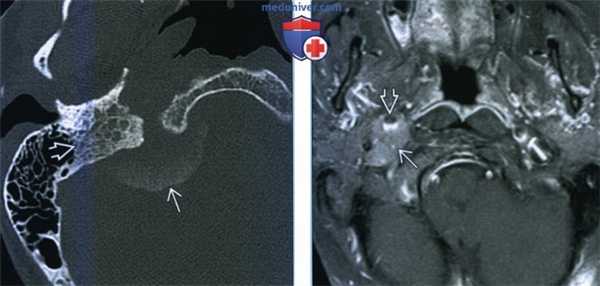

(Слева) КТ в костном окне, аксиальная проекция. Характерные инфильтративно-склеротические костные изменения в области основания черепа и яремного отверстия. Обратите внимание, что внутричерепная часть опухоли частично кальцифицирована.

(Справа) МРТ Т1ВИ FS с КУ, аксиальная проекция. Менингиома яремного отверстия распространяется вниз, в сонное пространство. Обратите внимание, что сонная артерия расположена спереди от опухоли. Подобные опухоли происходят из клеток арахноидального эндотелия. Увеличиваясь в размерах, менингиома начинает спускаться в сонное пространство. (Слева) МРТ Т1ВИ FS с КУ, аксиальная проекция. Крупная, накаливающая контраст опухоль правого сонного пространства, смещающая сонную артерию кпереди. Обратите внимание, что участки выпадения сигнала отсутствуют. Этот признак помогает дифференцировать менингиому от более распространенной опухоли-параганглиомы.

(Справа) МРТ Т1ВИ FS с КУ, коронарная проекция, тот же пациент. Крупная менингиома сонного пространства, исходящая из яремного отверстия. Обратите внимание, что в полости черепа имеется «хвост» из твердой мозговой оболочки -достаточно частая находка у пациентов, у которых менингиома основания черепа распространяется интракраниально.

(Справа) МРТ Т1ВИ FS с КУ, аксиальная проекция. Менингиома яремного отверстия распространяется вниз, в сонное пространство. Обратите внимание, что сонная артерия расположена спереди от опухоли. Подобные опухоли происходят из клеток арахноидального эндотелия. Увеличиваясь в размерах, менингиома начинает спускаться в сонное пространство.

(Слева) МРТ Т1ВИ FS с КУ, аксиальная проекция. Крупная, накаливающая контраст опухоль правого сонного пространства, смещающая сонную артерию кпереди. Обратите внимание, что участки выпадения сигнала отсутствуют. Этот признак помогает дифференцировать менингиому от более распространенной опухоли-параганглиомы.